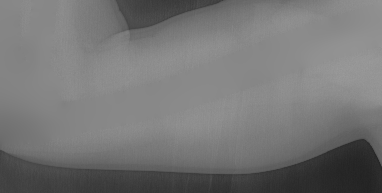

To tackle these problems, we propose to estimate the soft tissue image and bone image simultaneously without losing the linear relationship between image intensity and physical property of the imaging objects. Two examples from our method is shown in Fig. 1. The bone details are enhanced, which is theoretically guaranteed. The details of our method will be explained in later sections.

This equation can be efficiently solved by the convolution pyramid method [15], which has linear computational complexity. The estimated background image is shown in Fig. 5(c).

Several results from our method are shown in Fig. 7. The left column is the original input image. The right two columns are the soft tissue and bone image, respectively. It can be told that the soft tissue image is smooth as we assumed. Meanwhile, the bone image has better image contrast as desired. Moreover, our method can reach real-time performance on these X-ray images. The running time of our method on these images is reported in Table I.